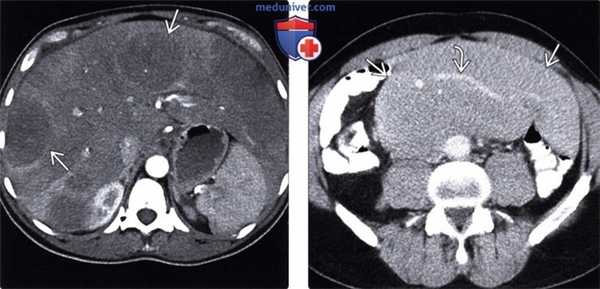

(Слева) При аксиальной КТ с контрастным усилением определяются множественные отдельно лежащие гиподенсные объемные образования в печени, а также выраженная диффузная инфильтрация большей части остальной паренхимы печени, выглядящей гиподенсной. При биопсии был подтвержден лимфоматозный характер инфильтрации.

(Справа) При аксиальной КТ с контрастом определяется большой конгломерат лимфатических узлов в брыжейке. Обратите внимание на сосуды внутри данного конгломерата, которые проходят сквозь него без сужения просвета или окклюзии, что является признаком, характерным для лимфомы.

(Слева) При аксиальной нативной КТ у пациента с трансплантатом почки визуализируются большие дольчатые объемные образования в подмышечной области слева, представляющие собой значительно увеличенные подмышечные лимфатические узлы.

(Справа) При аксиальной нативной КТ у этого же пациента визуализируются в значительной степени атрофически измененная собственная почка и правый надпочечник или забрюшинное объемное образование, обусловленное ПТЛЗ пациента. При ПТЛЗ может поражаться практически любой орган или группа лимфоузлов в организме, и любое мягкотканное объемное образование у реципиента трансплантата необходимо считать подозрительным на ПТЛЗ. (Слева) При аксиальной нативной КТ у пациента с трансплантированной почкой определяются объемные образования обоих надпочечников.

(Справа) На более каудальном аксиальном нативном КТ срезе у этого же пациента визуализируется трансплантат почки в правой подвздошной ямке. Имеет место также массивная тазовая лимфаденопатия. И лимфаденопатия, и объемные образования надпочечников являются проявлениями ПТЛЗ. (Слева) При аксиальной КТ с контрастным усилением у пациента с пересаженной печенью определяется большое объемное образование в трансплантате печени, которое окружает воротную вену и желчные протоки. Селезенка также вовлечена в процесс, что проявляется спленомегалией и множеством мелких гиподенсных узелков.

(Справа) При аксиальной КТ с контрастным усилением у этого же пациента выявлены увеличенные портакавальные лимфоузлы и лимфоузлы в воротах печени, представляющие собой проявления ПТЛЗ. Обратите внимание на билиарный стент, установленный с целью коррекции выраженного сдавливания общего желчного протока увеличенными лимфоузлами и объемным образованием печени.